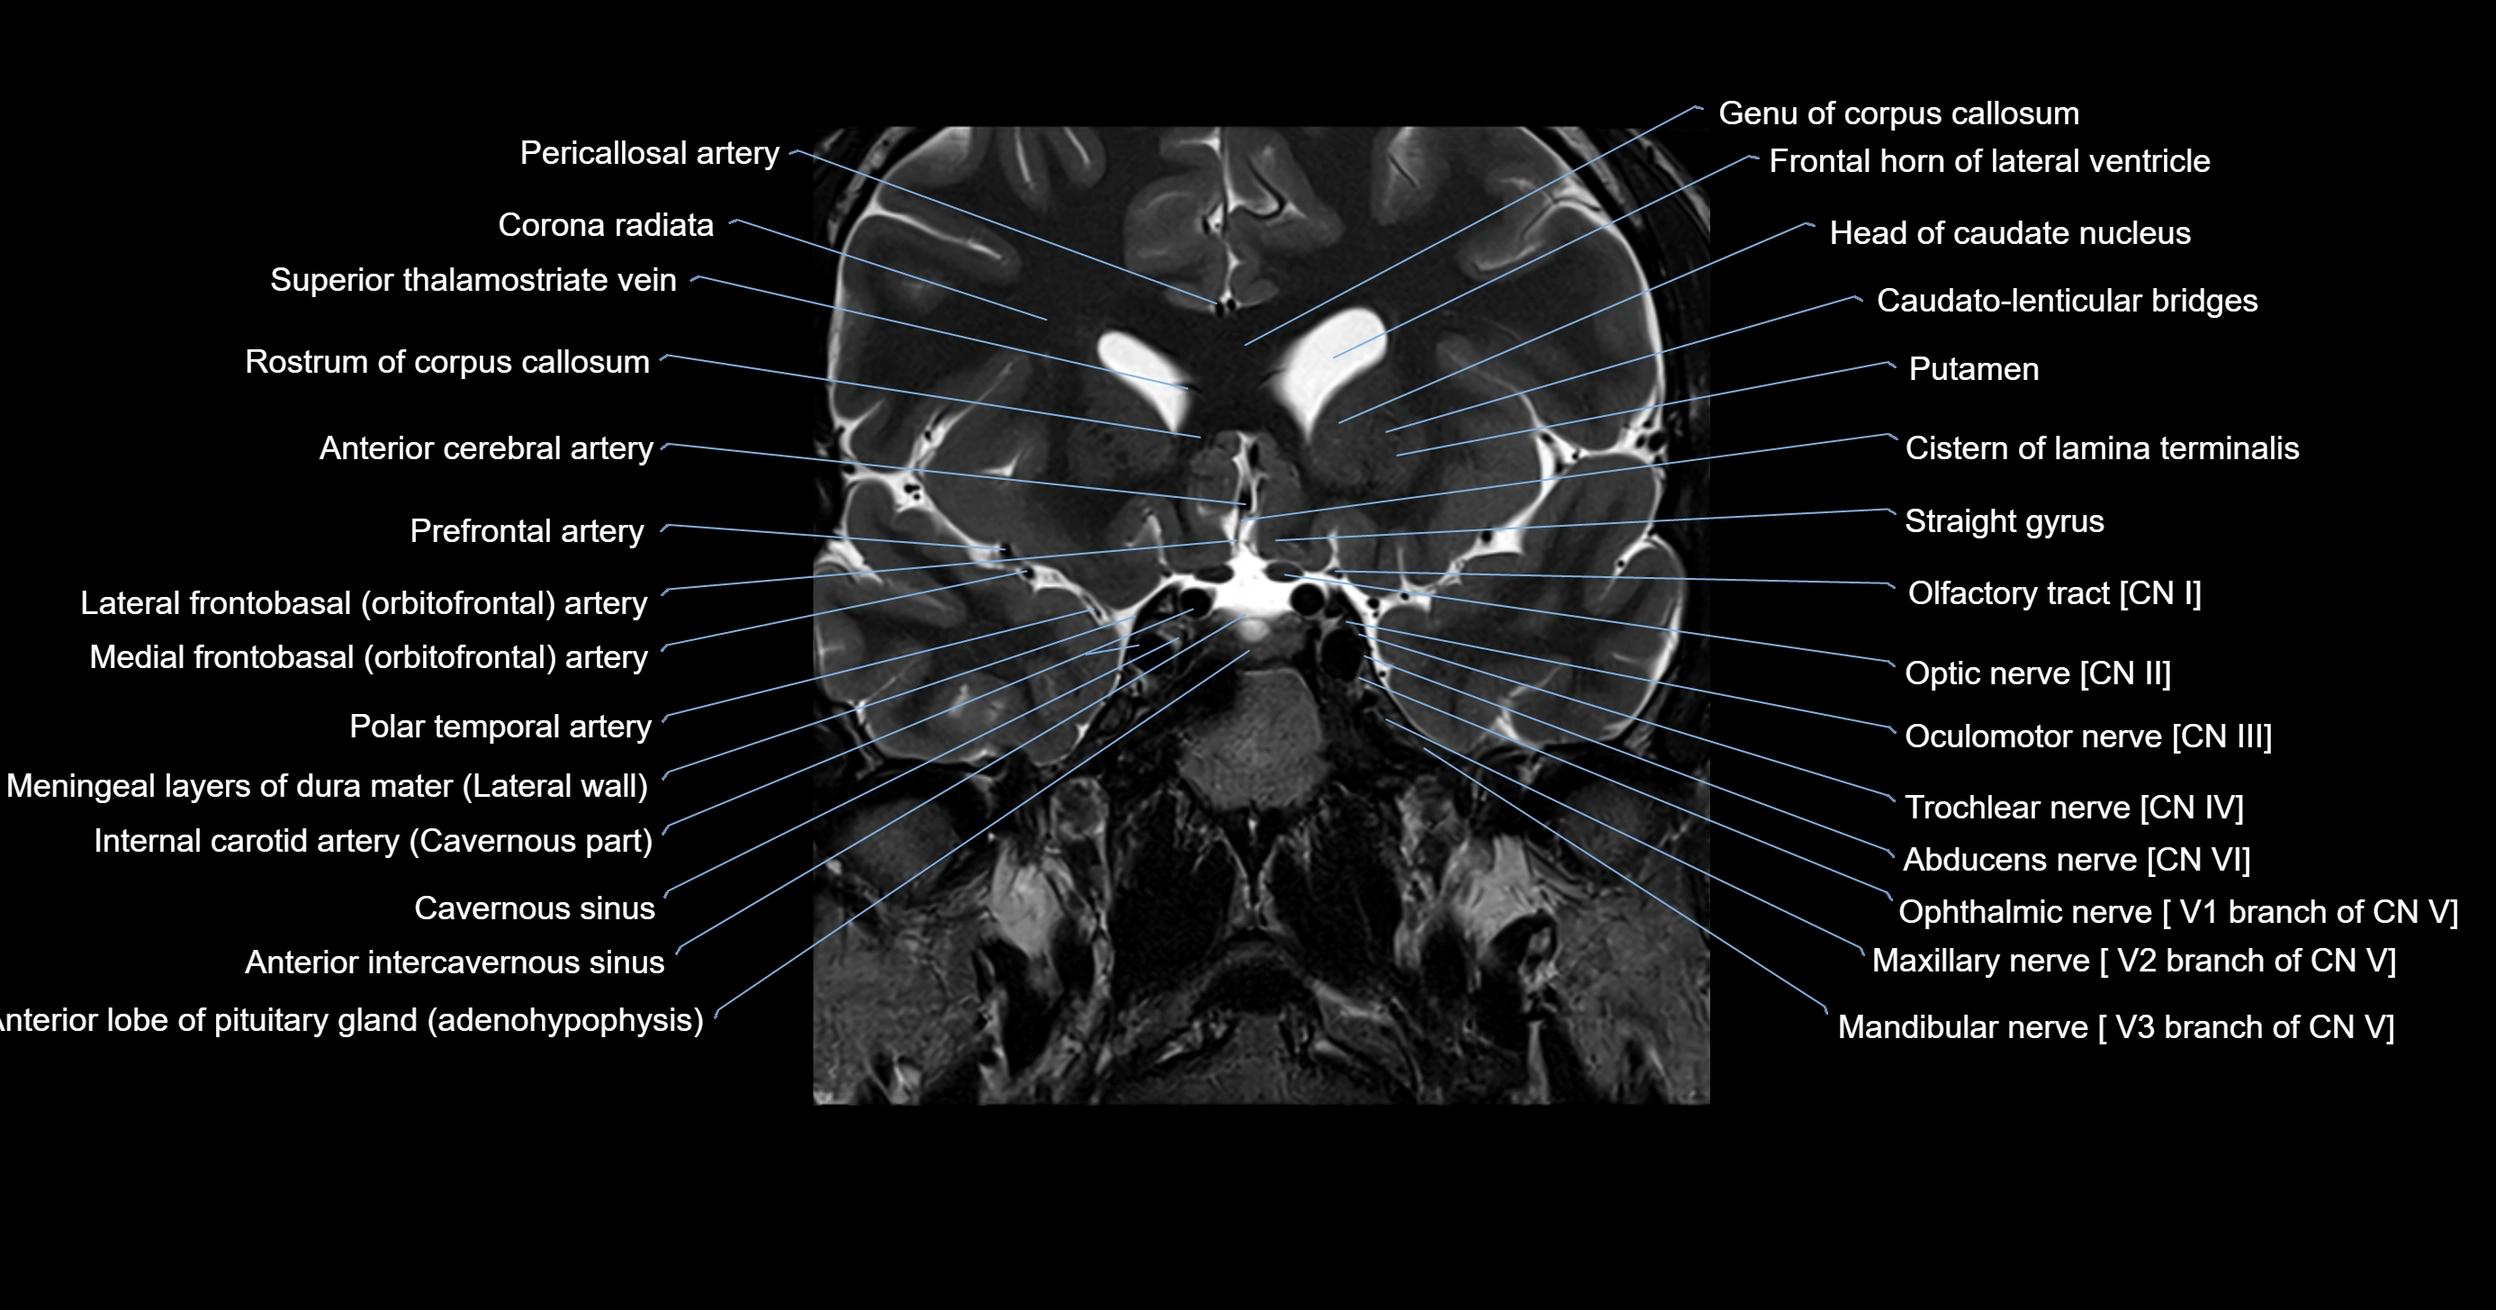

- Abducens nerve (Cranial nerve VI)

- Anterior intercavernous sinus

- Anterior limb of internal capsule

- Anterior lobe of pituitary gland

- Cistern of lamina terminalis

- Corona radiata

- Frontal horn of lateral ventricle

- Genu of corpus callosum

- Head of caudate nucleus

- Lateral frontobasal artery

- Lateral geniculate body

- Mandibular nerve

- Maxillary nerve

- Medial frontobasal artery

- Oculomotor Nerve (Cranial Nerve III)

- Olfactory Nerve (Cranial Nerve I)

- Olfactory tract

- Optic Nerve (Cranial Nerve II)

- Pericallosal artery

- Polar temporal artery

- Putamen

- Rostrum of corpus callosum

- Superior hypophyseal artery

- Superior thalamostriate vein

- Trigeminal nerve (Cranial nerve V)

- Trochlear nerve (Cranial nerve IV)

- cavernous sinus